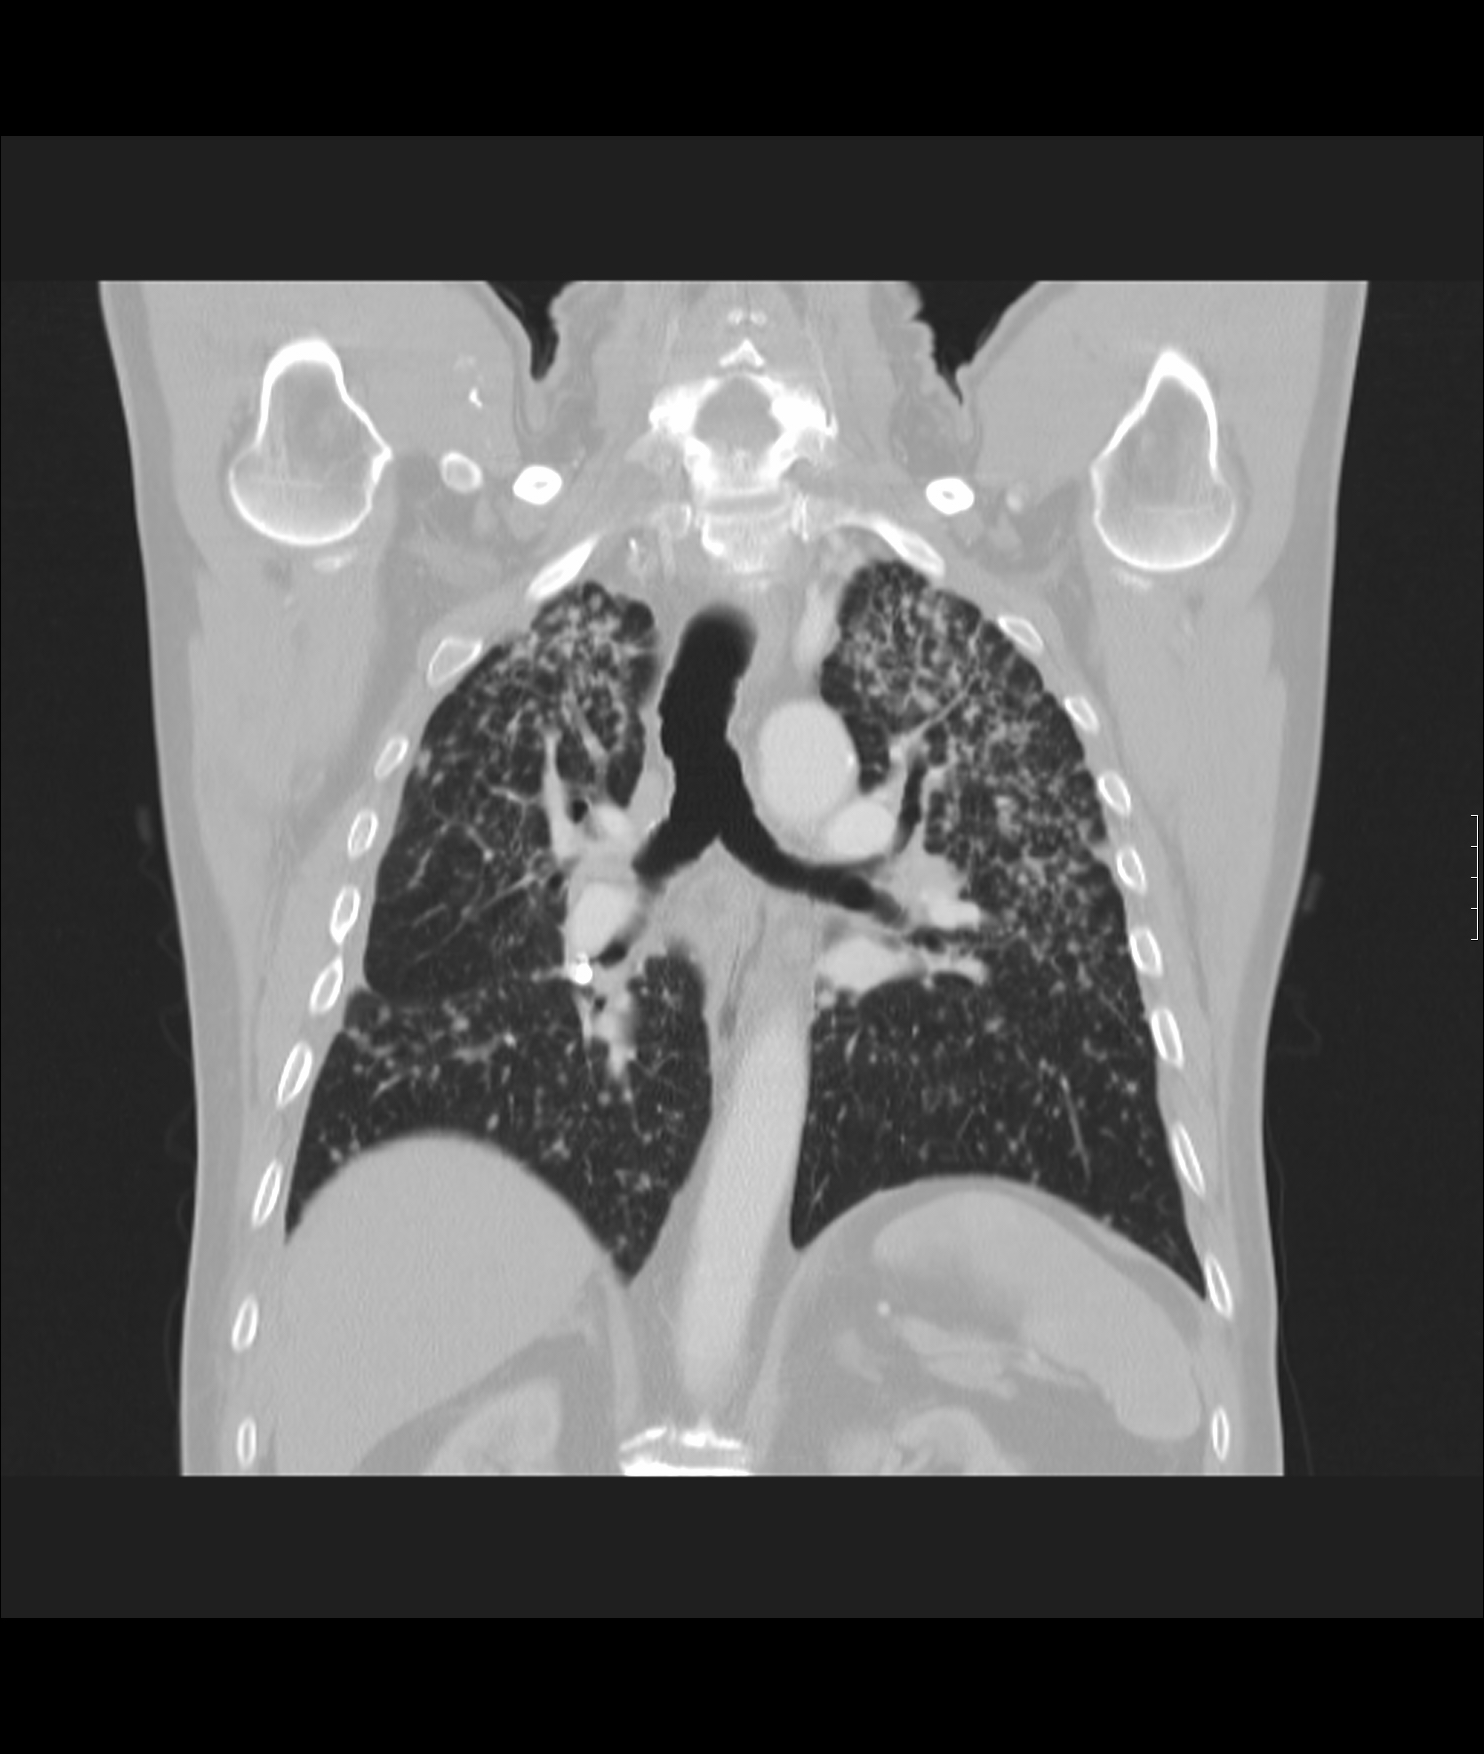

4: Miliary pattern: sarcoidosis, CT, lung window. Axial image and sagittal reformat.

A 67 year old female suffering from COPD. Bilateral rough branching interstitial widening and patchy, miliary nodules with perihilar dominance along the bronchovascular fibres and the fissures.